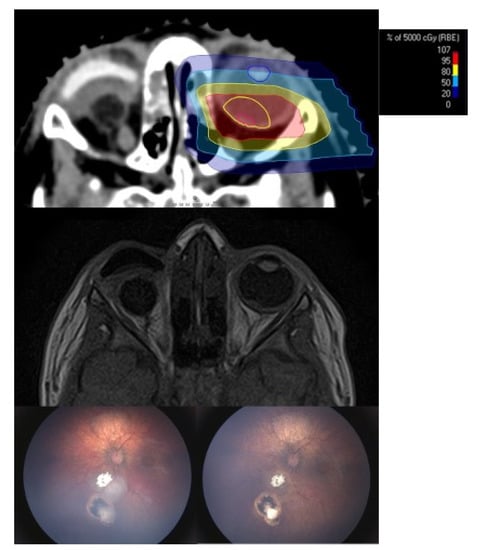

Treatment Technique